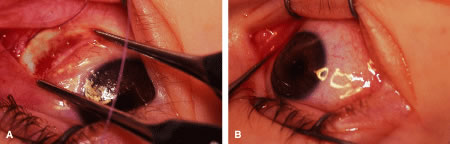

Incision is made into the conjunctiva at the limbus (Fig. 64).

|

The assistant elevates the conjunctiva while the surgeon uses a Stevens' hook to elevate the rectus muscle (Fig. 65). A Jameson muscle hook is passed under the muscle tendon in a plane that is tangential to the scleral surface, about 3 mm behind the tented rectus muscle insertion. Figure 66 shows the rectus muscle on the Jameson hook.

|